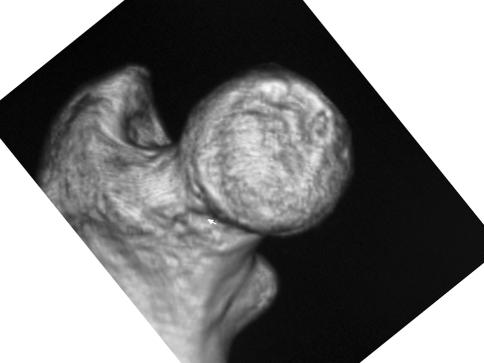

The natural history of osteonecrosis of the femoral head is generally thought to be one of progressive deterioration if no intervention is undertaken. However, it is unknown whether surgical intervention is beneficial for patients with a small region of osteonecrosis. We observed rapid improvement of MRI findings after rotational acetabular osteotomy (RAO) was performed in a young patient with osteonecrosis of the femoral head. The band-like low signal area on T2-weighted images almost resolved by six months after surgery. He returned to work as an electrician by six months after surgery. Early surgical intervention such as RAO that alters the mechanical force acting on the necrotic region of the femoral head may accelerate the recovery of osteonecrosis and the improvement of symptoms.

股骨头坏死的自然病程通常被认为是进行性恶化的,如果不进行干预的话。然而,对于股骨头坏死中存在小区域骨坏死的患者,手术干预是否有益尚不清楚。我们观察到一位年轻的股骨头坏死患者接受了旋转髋臼截骨术(RAO)后,其 MRI 发现迅速改善。手术后六个月,T2 加权图像上的带状低信号区几乎完全消失。手术后六个月,他恢复了电工的工作。像 RAO 这样的早期手术干预可以改变作用于股骨头坏死区域的机械力,从而可能加速骨坏死的恢复和症状的改善。